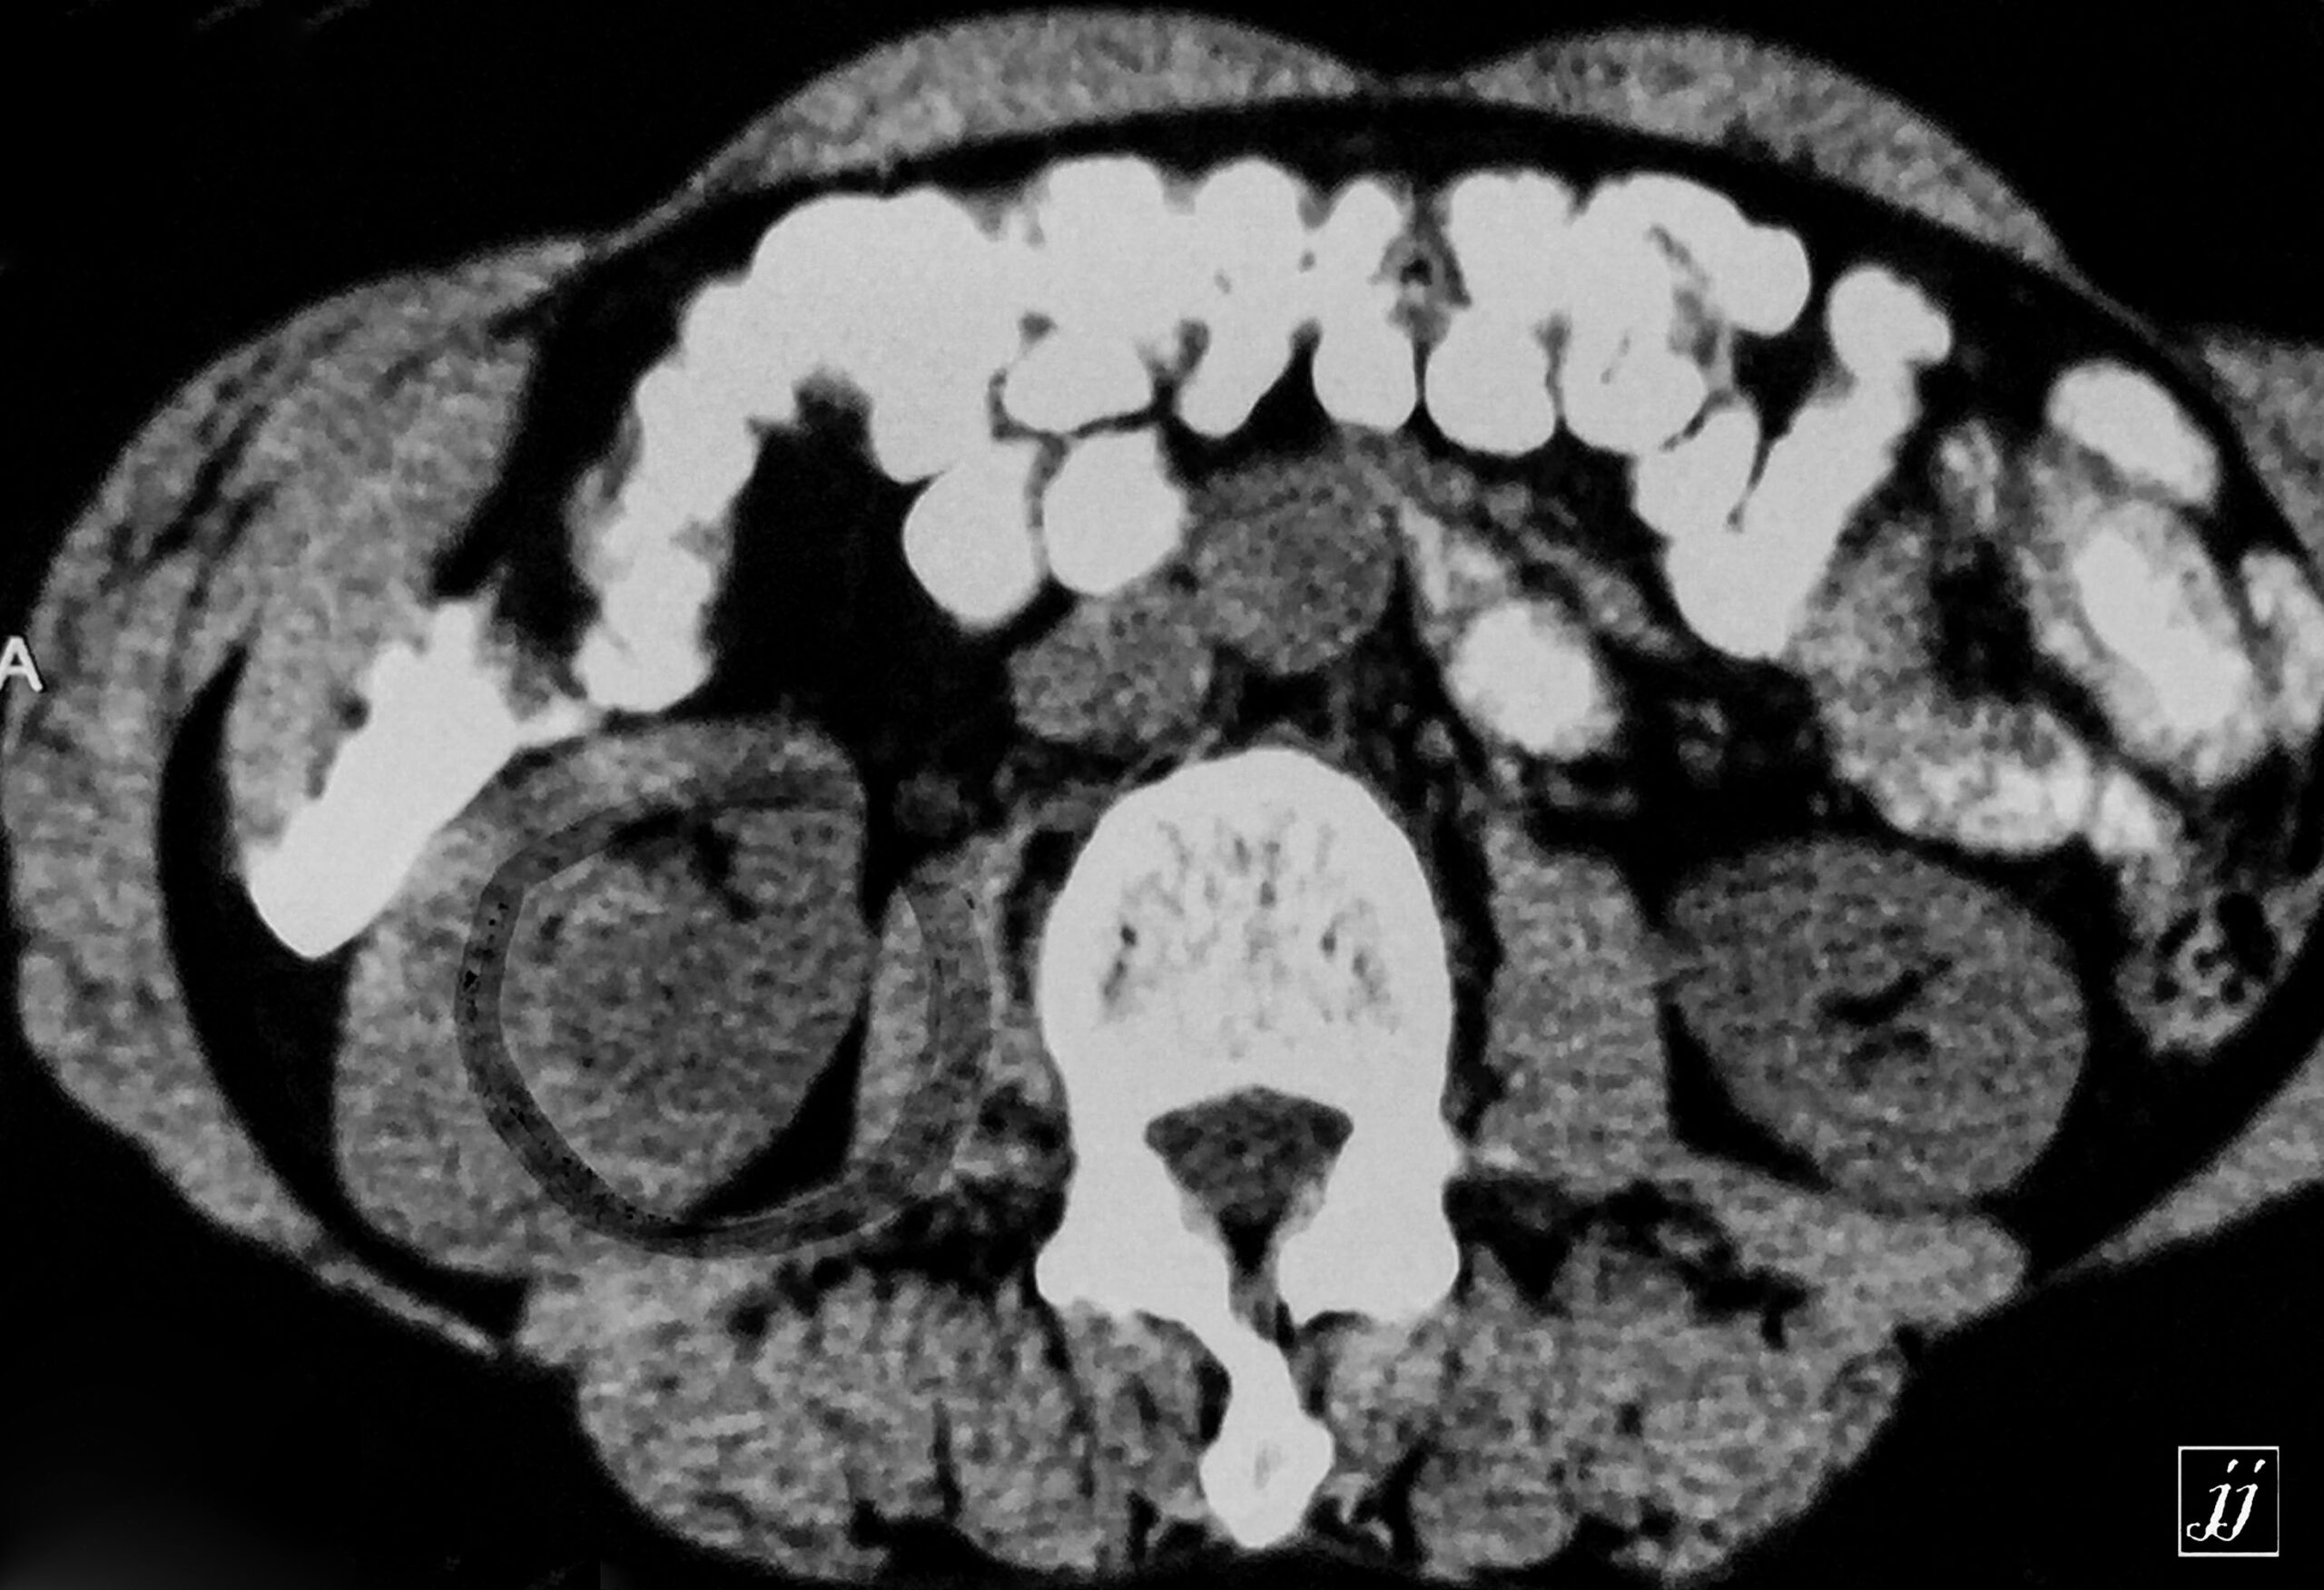

Abdomen- para pelvic right renal tumor (11)